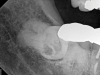

Fig 5. Case 2: Periapical imaging of the maxillary right (Fig 5) and mandibular right (Fig 6) quadrants.

Figure 5

Fig 6. Case 2: Periapical imaging of the maxillary right (Fig 5) and mandibular right (Fig 6) quadrants.

Figure 6

On clinical examination, marginal leakage was noted around the large composite restoration on the occlusal surface of tooth No. 2. Recurrent caries was noted on the buccal margin of the bucco-occlusal composite restoration on tooth No. 30. Tooth No. 1 was not visible within the oral cavity. Teeth Nos. 2 and 30 were both nonresponsive to pulp sensitivity testing, whereas neighboring control teeth responded normally to cold and electric pulp testing. All posterior teeth in the maxillary and mandibular right quadrants were normally responsive to percussion and palpation testing. No swellings, sinus tracts, or periodontal defects were noted.

Periapical imaging revealed evidence of a prior pulpotomy on tooth No. 2, without obvious signs of apical pathology (Figure 5). A deep restoration with evidence of periapical pathology was seen on periapical imaging of tooth No. 30 (Figure 6). The diagnosis for tooth No. 2 was previously initiated treatment with normal periapical tissues, while the diagnosis for tooth No. 30 was pulpal necrosis with symptomatic apical periodontitis. Although it was clear that both teeth would eventually require definitive endodontic treatment or extraction, the source of the current severe pain remained unclear.

Selective anesthesia was utilized in order to differentiate the source of the pain to facilitate clinical decision making and triage emergency care. Initial administration of 1.7 cc 4% septocaine with 1:100,000 epinephrine via buccal infiltration on tooth No. 2 resulted in no reduction in pain. However, after 10 minutes, symptoms began to localize to the lower right quadrant. Further administration of 1.7 cc 2% xylocaine with 1:100,000 epinephrine via inferior alveolar nerve block resulted in complete resolution of pain. Given the absence of pain following mandibular anesthesia, tooth No. 30 was clearly the current source of pain and required immediate treatment. A pulpectomy was completed on tooth No. 30 to alleviate the patient's symptoms. Follow-up the next day confirmed resolution of all symptoms.